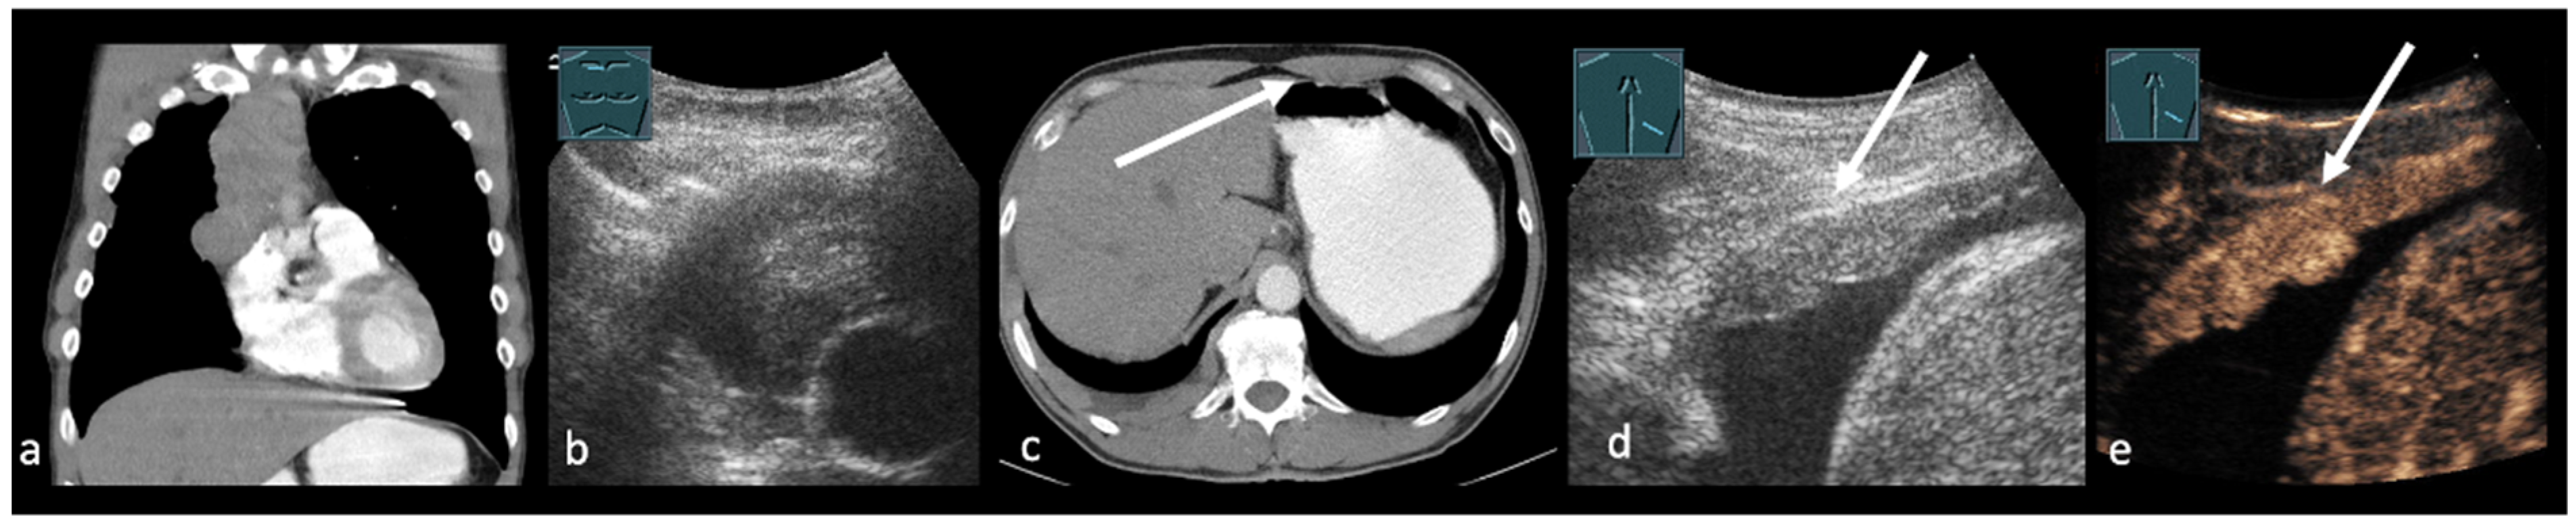

3. Transthoracic Ultrasound in the Evaluation and Characterizing of Local Tumor Size (T-Stage)